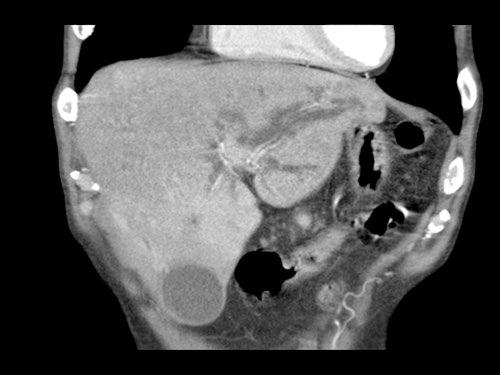

CT axial cho thấy:

- Khối u ở thân tụy (đầu mũi tên trắng).

- Tiếp xúc khu trú < 90º với động mạch mạc treo tràng trên (SMA).

- Tiếp xúc rộng hơn từ 90º – 180º với SMV, SMV bị hẹp nhẹ và biến dạng (mũi tên vàng).

- Giãn ống tụy

Tái tạo mặt phẳng coronal cho thấy:

- Bất thường bờ viền thành SMV được nhận thấy rõ hơn trên tái tạo coronal này (mũi tên).

- Huyết khối trong các nhánh bên của SMV (mũi tên xanh nhỏ).